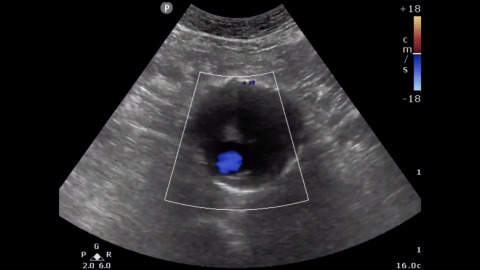

RUSH Exam (Rapid Ultrasound in Shock and Hypotension)

Dr. Jacob Avila teaches the HI-MAP approach to the RUSH exam, which stands for Heart, IVC, Morrison's Pouch (for the FAST exam component), Aorta, and Pulmonary.